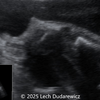

A 33-year-old nullipara with non-contributory medical history presented at 20 weeks, 6 days based on an early scan. Ultrasound revealed the following findings. There were no other apparent abnormalities. What is the most probable diagnosis?